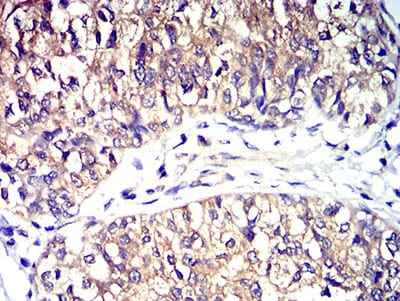

| IHC | 1/200 - 1/1000 | Human,Mouse,Rat |

CD195 antibodies are vital tools for studying CCR5 expression, function, and signaling in diseases like HIV/AIDS, autoimmune disorders, and cancers. They are used in flow cytometry, immunohistochemistry, and functional assays to characterize immune cell subsets or evaluate receptor modulation. Some therapeutic antibodies or small molecules targeting CCR5 aim to block inflammatory pathways in conditions such as rheumatoid arthritis or to inhibit cancer metastasis. Additionally, the CCR5Δ32 mutation, which confers natural resistance to HIV, has spurred gene-editing approaches using CRISPR/Cas9. with CD195 antibodies serving as validation tools.